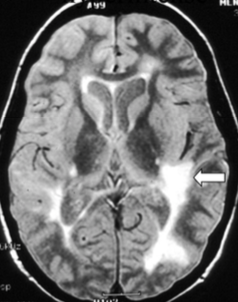

What do you see here?

What is one of the typical distributions of MS plaques?

In addition to the classic periventricular plaques, where else in the brain can these be in MS pts?